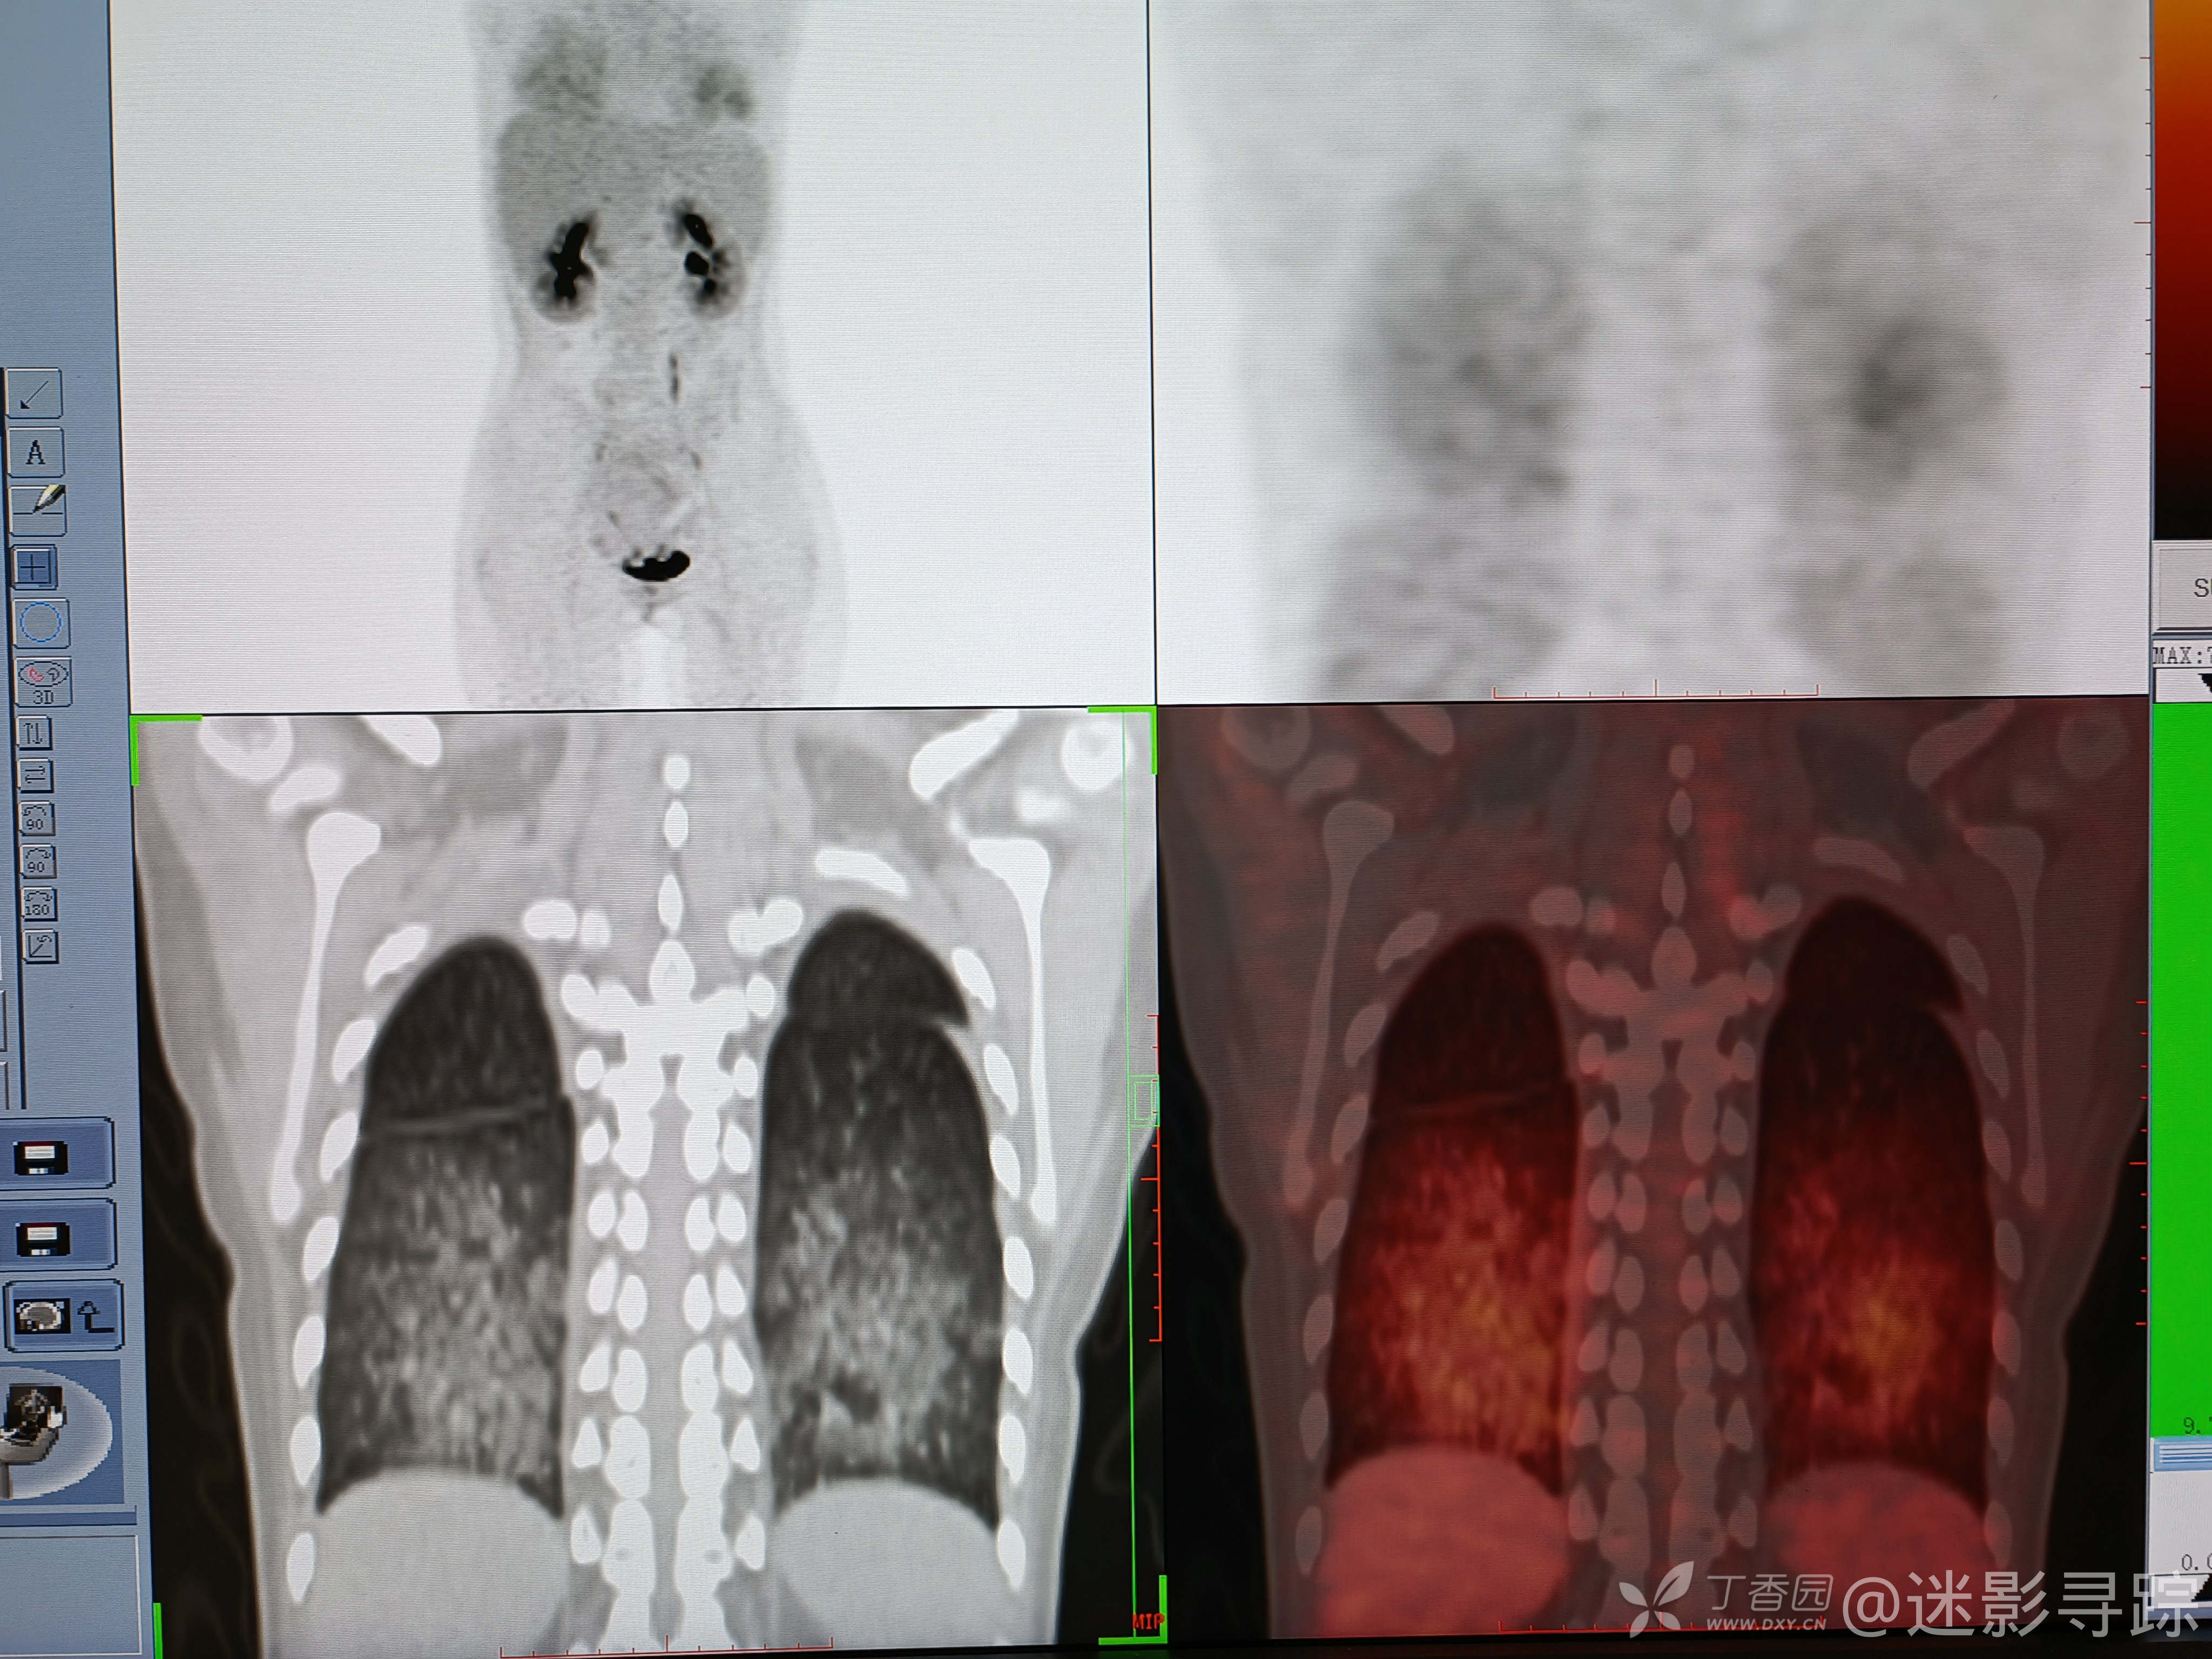

病例白血病髓外浸润化疗及移植后,双肺弥漫高密度影,考虑?补充PETCT,已公布结果!

女性,26岁,确诊白血病1年余,后发现髓外浸润,化疗后明显好转,后移植治疗。现因发热1周就诊。